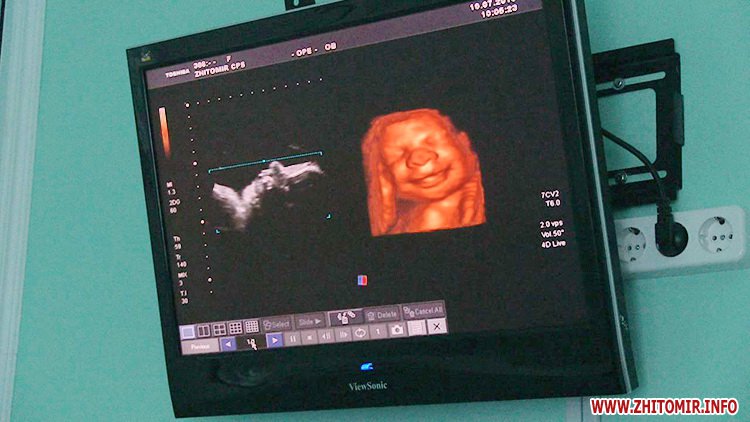

Чисельні датчики, надсучасні комп'ютери, а найголовніше – високопрофесіональні фахівці, у Житомирському обласному перинатальному центрі вже 10 років працюють над тим, щоб новонароджені і їх мами були здоровими.

Результат гарантує найсучасніше медичного устаткування і важка щоденна праця лікарів.